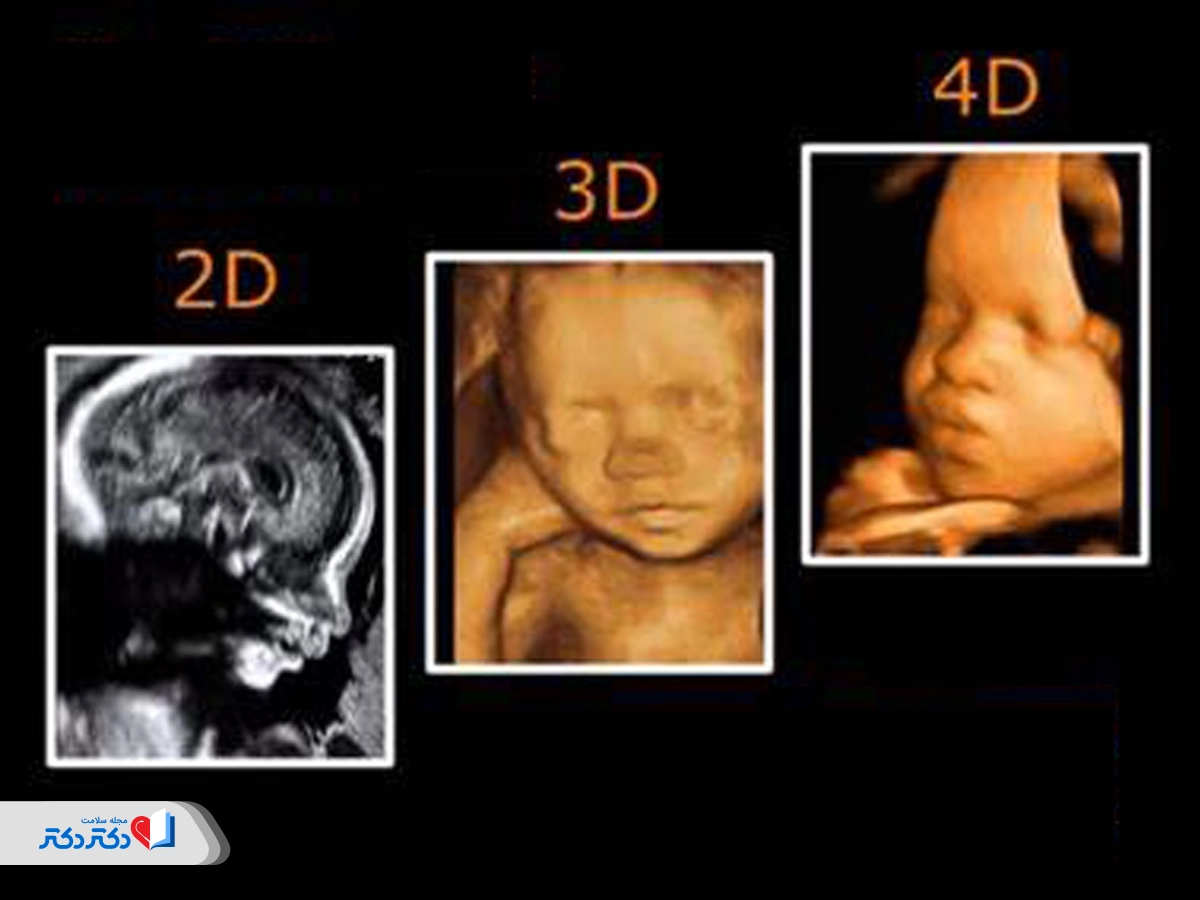

تفاوت سونوگرافی سهبعدی با سونوگرافی معمولی یا دوبعدی

در تمام انواع سونوگرافی از امواج صوتی برای ایجاد تصویری از جنین موجود در رحم استفاده میشود ولی سونوگرافی سهبعدی و دوبعدی تفاوتهایی با هم دارند. سونوگرافی دوبعدی روش تصویربرداری استانداردی است که تصاویر مسطح، دوبعدی و سیاهوسفید از جنین تولید میکند. از سونوگرافی دوبعدی عمدتا برای تولید تصاویری واضح برای ارزیابیهای پزشکی، ازجمله بررسی موقعیت و رشد جنین، بررسی موقعیت جفت و اندازهگیری مایع آمنیوتیک، استفاده میشود. در مقابل در سونوگرافی سهبعدی هزاران تصویر دوبعدی گرفتهشده از زوایای مختلف در کنار هم قرار میگیرند تا یک تصویر سهبعدی ایجاد شود. با این روش تصاویری زنده از ویژگیهای جنین مانند صورت و اندامها خواهیم داشت.

تفاوت سونوگرافی سهبعدی با سونوگرافی چهاربعدی

سونوگرافی چهاربعدی مشابه سونوگرافی سهبعدی است با این تفاوت که در آن عنصر زمان نیز اضافه میشود و حرکت جنین نشان داده میشود. در سونوگرافی چهاربعدی میتوانید خمیازهکشیدن، لگدزدن یا حتی مکیدن انگشت شست جنین را در زمان واقعی ببینید، البته تا زمانی که فضای کافی برای تکانخوردن او وجود داشته باشد.